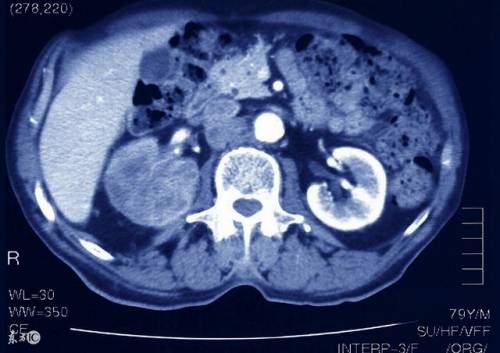

肾癌的临床诊断主要依靠超声、CT 和 MRI。一般情况下,肾癌早期并无明显症状,很多都是在体检时被发现。其中,B 超可以发现 1 公分甚至小于 1 公分的占位,若发现占位,就需要进行进一步的检查,比如 CT 或者是核磁共振检查。CT 可以发现肾内 5 毫米的病变,也可显示肿瘤与其他组织的侵犯关系。磁共振比 CT 更加准确,可确定肿瘤通过淋巴结的转移情况。但最终的确诊,需要通过病理检查来确诊,病理学检查是确诊肾癌的重要检查手段,可以对肾占位做一个穿刺,确定占位组织是否为癌组织。